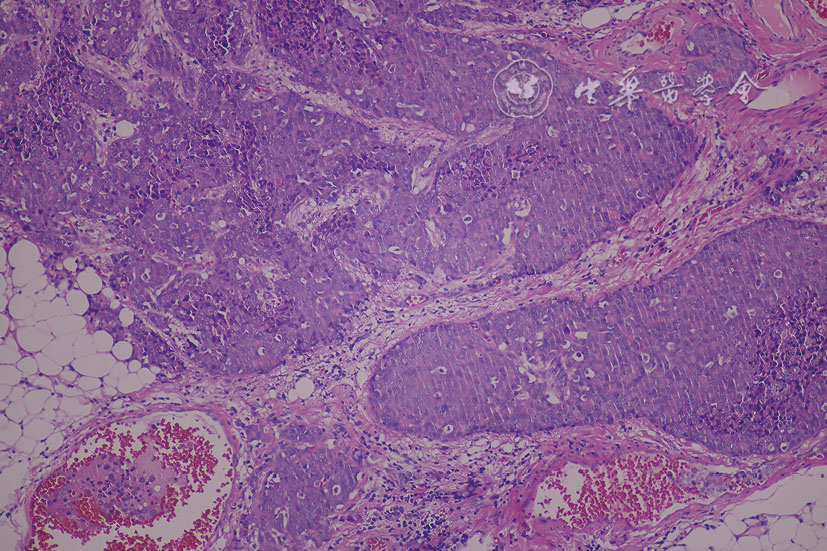

图4 男性隐匿性乳腺癌患者右侧腋窝皮下肿块切除术后病理图(HE ×200) 注:肿瘤细胞呈巢团状排列,符合浸润性导管癌形态